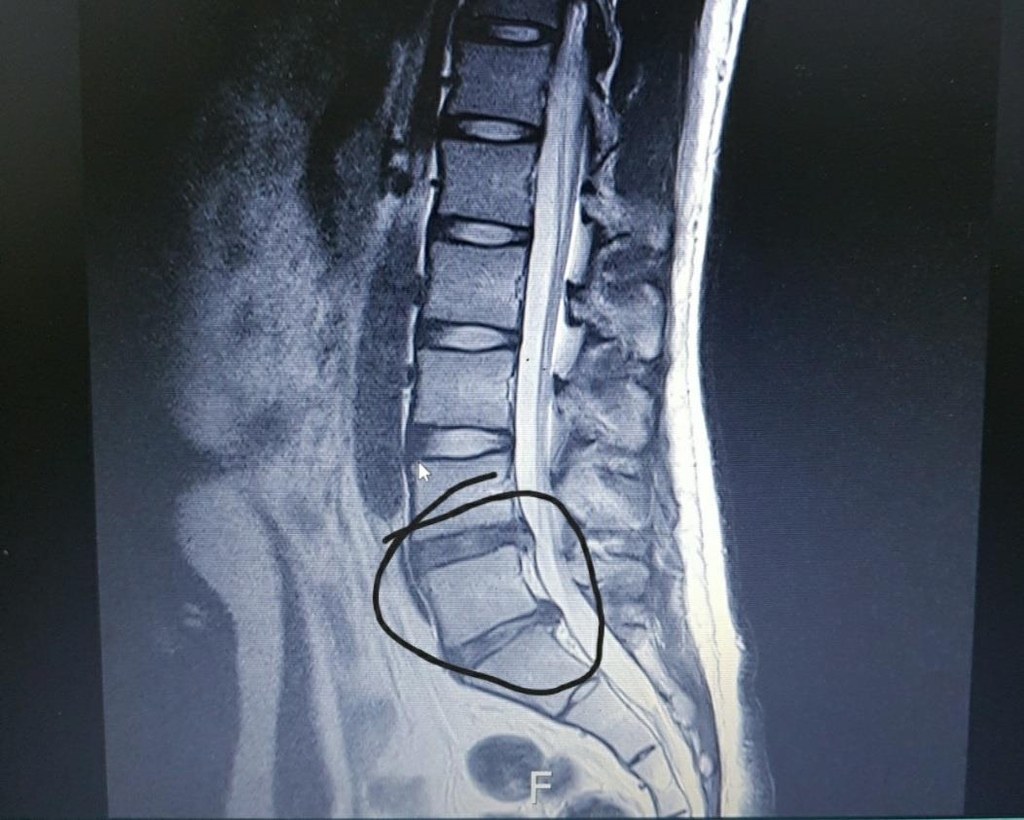

허리디스크는 척추의 구조를 이해하는 것이 중요합니다. 척추는 여러 개의 척추뼈로 이루어져 있으며, 이 사이에 디스크가 위치하고 있습니다. 디스크는 젤리같이 부풀어 있는 내부와 외부 섬유링으로 이루어져 있어 충격을 흡수하는 역할을 합니다. 그러나 여러 요인, 예를 들어 무리한 운동, 잘못된 자세, 노화 등으로 인해 디스크가 손상되거나 탈출하게 되면 심각한 통증을 유발할 수 있습니다.

허리디스크 증상은 다양한 형태로 나타날 수 있으며, 이를 통해 문제가 발생하고 있음을 인식할 수 있습니다. 일반적으로 허리디스크의 증상은 허리 통증, 다리 저림, 근력 약화, 통증의 위치에 따라 다양하게 나타나기 때문에 이러한 사항들을 잘 이해해야 합니다.